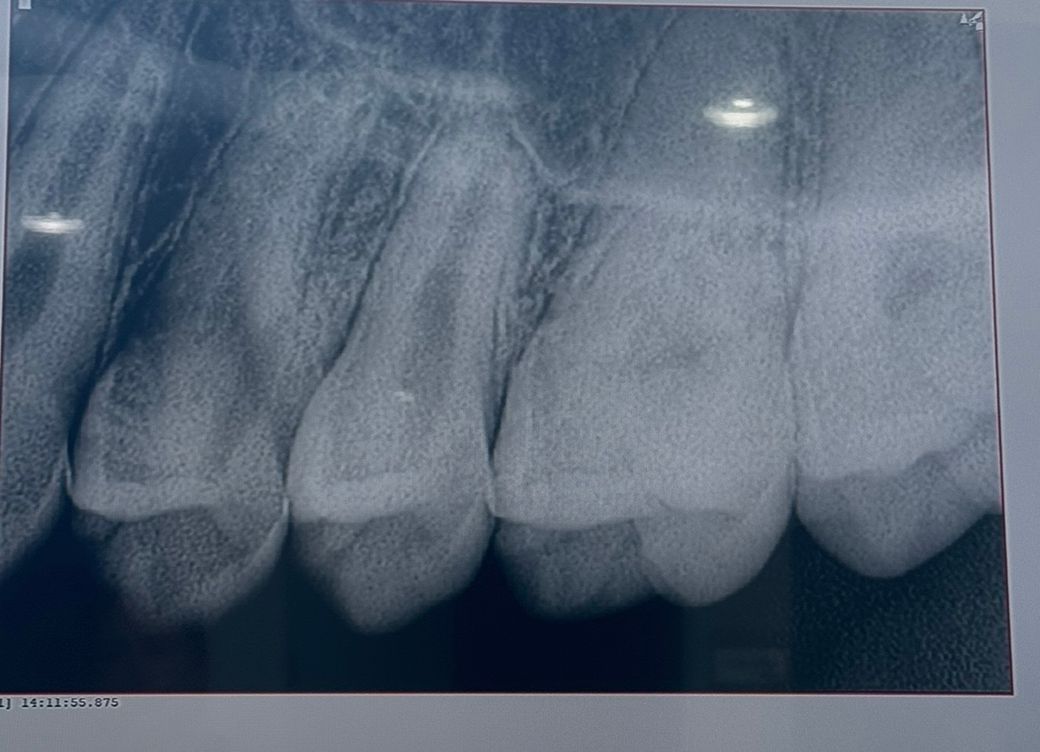

25~26 치아고 첫번째, 세번째 사진이 최근 두번째 사진이 올해 2월 입니다 인접면 충치가 맞는지 얼마나 진행되었는지 궁금합니다

• 1번 째 사진

엑스레이 상에서 명확히 관찰되지는 않는 것으로 보이며 관리 하면서 지켜봐도 될 것 같습니다.

엑스레이 상으로는 인접면 충치가 심해 보이진 않으니 일단은 관리를 해서 사용해보셔도 될것같습니다.

25~26 치아고 첫번째, 세번째 사진이 최근 두번째 사진이 올해 2월 입니다 인접면 충치가 맞는지 얼마나 진행되었는지 궁금합니다 -> 25,26 사이 인접면 충치 크게 문제 없어 보입니다

사진으로 봤을 경우에는 인접면에 어두운 면이 보입니다. 충칠 가능성이 높지만 정확한 확인은 육안으로 확인을 해봐야 알 수 있을것으로 생각됩니다.

자세한 확인을 위해서 치과에서 진료를 받아보는 것을 권유드립니다.